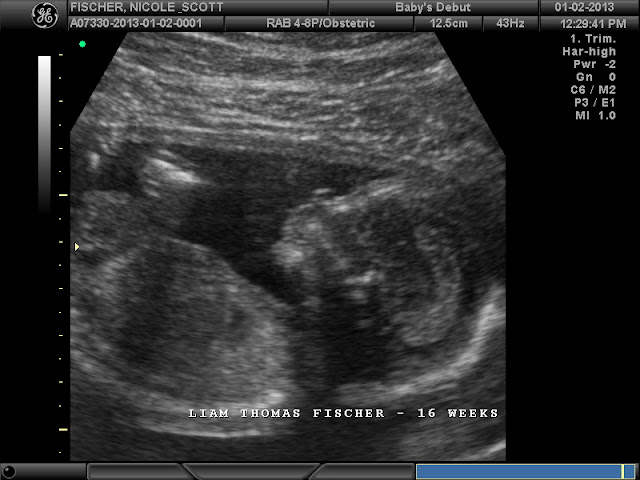

Liam Thomas Fischer

That's his foot up to his face, he looks like a toe sucker lol. Liam takes after his Mommy I guess, his arms are up with his fist alongside his head. (The way I sleep) He kept his hands up there the whole time, even wiggling his fingers enough to flip us the bird a few times... :)

The moment the tech put the wand/probe thingy on me and I saw that there really was something inside of me, I cried. Being that I don't have many symptoms at all and havent felt him moving around yet has definitely made it a dream like thing. And seeing him, that he's really in there...it was so reassuring and amazing!!

We did see him in 3D, but we only got 2D photos, which I'm glad, he didnt look like much in 3D. He's not plump enough to really get a good idea of what he will look like anyways.